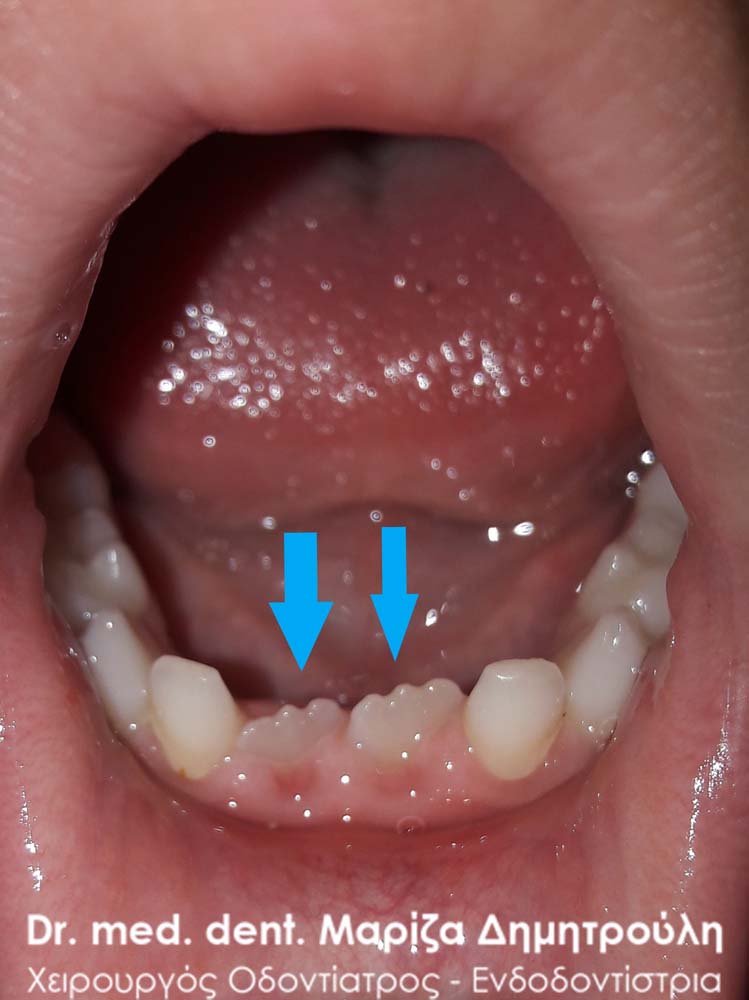

One month after the primary tooth extraction

Extraction of double primary tooth